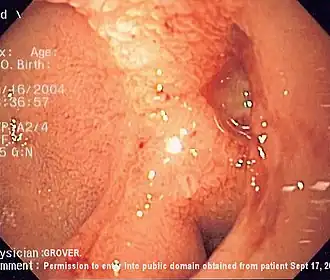

| Endoscopia de uma úlcera duodenal com base limpa. | |